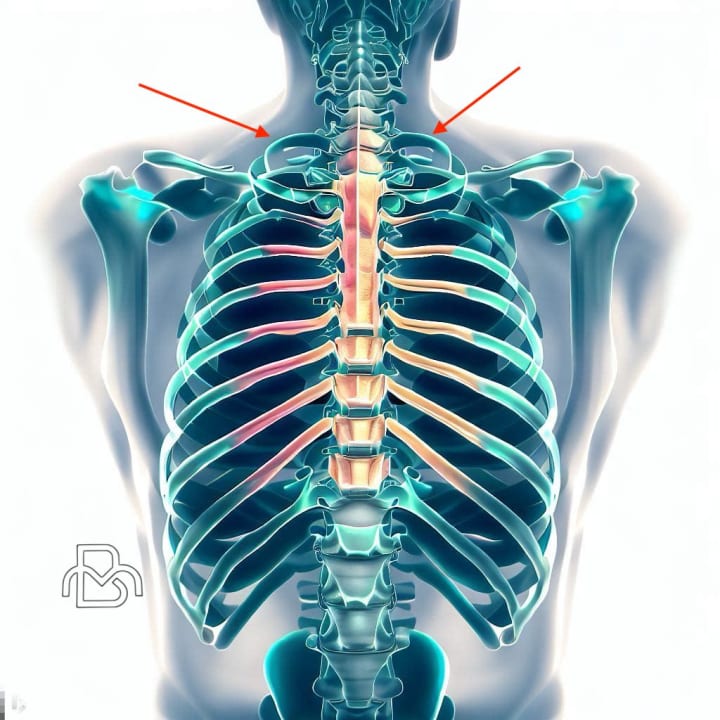

•Trauma or injury - Acute injuries like clavicle fractures, first rib fractures or whiplash injuries usually occur in the earlier decades of life and may lead to post-traumatic compressions, especially if healing does not proceed properly. The trauma itself or subsequent inflammation can narrow passages, entrap nerves or limit muscle function resulting in pain and disability.